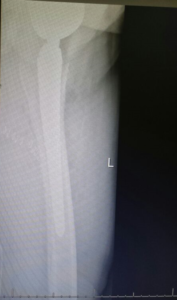

- Femur Fractures.

if the fracture is displaced, surgery may be needed to put the bone back into the correct position and fix the bone with Plates & screws or nails for adequate healing to occur.